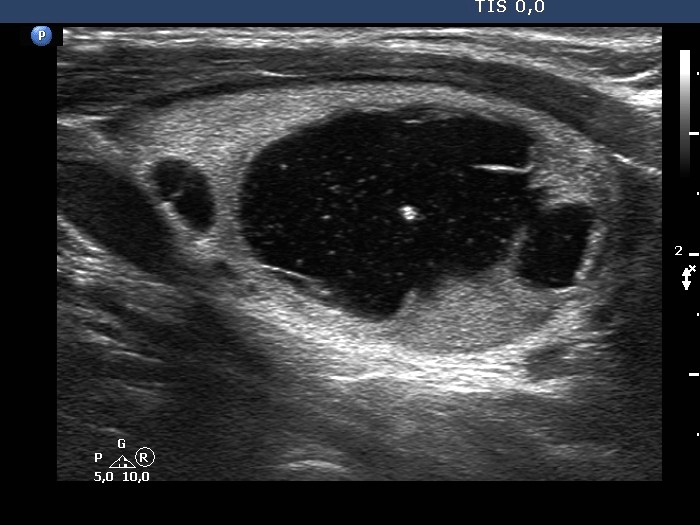

Second examination 4 years later (second and third rows of images):

Clinical presentation: The patient had no complaints.

Palpation: unchanged.

Result of blood test: TSH 1.52 mIU/L.

Ultrasonography. The cystic nodule had refilled. The presentation remained the same.Seven mL brown fluid was aspirated. Cytology: benign, cystic lesion.

Suggestion: ultrasound in two years.